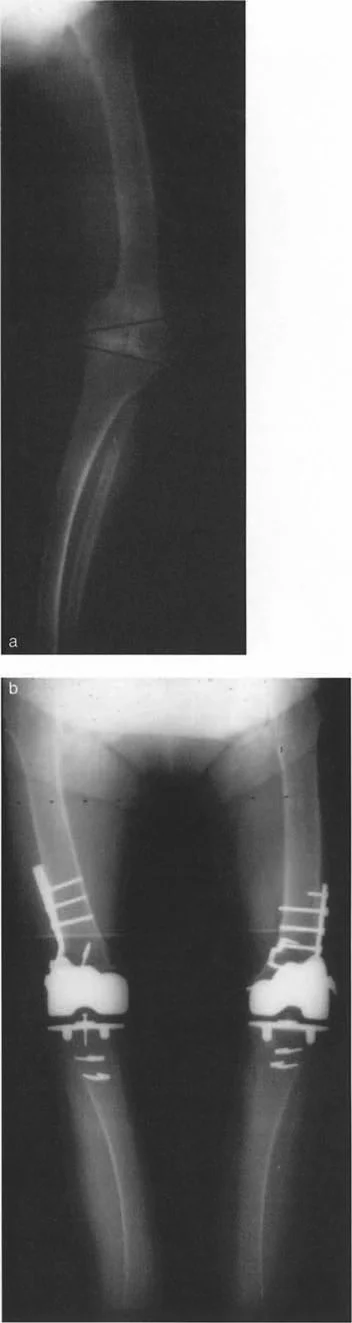

- جراحات قطع العظم وتقويم المحاور

- استبدال المفاصل في حالات التشوه الشديد

في حين أن التشوهات الديناميكية تُناقش غالبًا في سياق أمراض الأعصاب والعضلات لدى الأطفال، فإن المبادئ البيوميكانيكية التي تحكمها تنطبق عالميًا على إعادة بناء العظام لدى البالغين. يشمل ذلك سيناريوهات إعادة البناء المعقدة للغاية، مثل استبدال مفصل الركبة الكلي (TKR) واستبدال مفصل الورك الكلي (THR) المرتبطة بالانحرافات الشديدة خارج المفصل. إن فهم الأذرع الرافعة هو المتطلب الأساسي لإتقان هذه التقنيات المتقدمة في جراحة المفاصل وقطع العظم، وهو ما يتقنه الأستاذ الدكتور محمد هطيف في ممارسته اليومية.

- الالتئام الخاطئ للكسور (Malunions): عندما تلتئم العظام بعد الكسر في وضع غير صحيح، يمكن أن يؤدي ذلك إلى تغييرات في المحور الميكانيكي للأطراف وتشويه في أذرع الرافعة.

- التهاب المفاصل التنكسي (Osteoarthritis): في المراحل المتقدمة، يمكن أن يؤدي تآكل الغضاريف وتغير شكل المفصل إلى انحرافات في المحور الميكانيكي، مما يفاقم خلل وظيفة الذراع الرافعة ويؤدي إلى زيادة الضغط على المفصل.